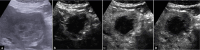

Intrahepatic cholangiocarcinoma (ICC) is a rare, heterogeneous, highly lethal tumor of the biliary tract. Due to the lack of effective treatments, an early identification of ICC is essential to achieve the best outcome in terms of therapy and prognosis aiming for a curative intent. ICC may arise on a normal liver or with an underlying liver disease, making the diagnosis more difficult and complex. Contrast-enhancement ultrasound (CEUS) is an accurate procedure able to detect ICC-specific contrast vascular pattern, and thus facilitating the correlation between radiological and histopathological findings with high specificity and sensitivity. CEUS has been shown to have a high diagnostic potential in the diagnosis of ICC thanks to the possibility of studying in real time the intralesional microcirculation and evaluating the precocity of the enhancement of the lesion during the arterial phase. All these features allow to differentiate the ICC from hepatocarcinoma (HCC) with high sensitivity and specificity. Furthermore, CEUS is a rapid, non-invasive, non-nephrotoxic or non-allergenic tool. The only limitations CEUS may have are related to the disease site and patient characteristics (obesity) and compliance, including the operator's experience. A clinical evaluation of the patient, together with tumor markers and biochemical tests assessment, to differentiate ICC from HCC are highly suggested.